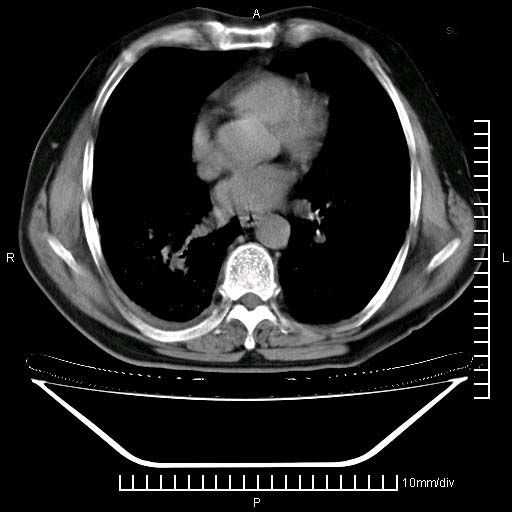

标题: CT24043:胸部增强:男性,60岁 [打印本页]

标题: CT24043:胸部增强:男性,60岁

既往肺结核,近10几天,咳嗽,咳痰,右侧胸痛,疼痛较明显,右上肺斑块考虑结核灶胸膜粘连,增强,可惜动脉期没有定好,未见强化,可延迟4分后又见较明显强化,中心见低密度影,如果说结核是边缘强化,可这个灶强化的面积挺大的,让人很挠头。

动脉期